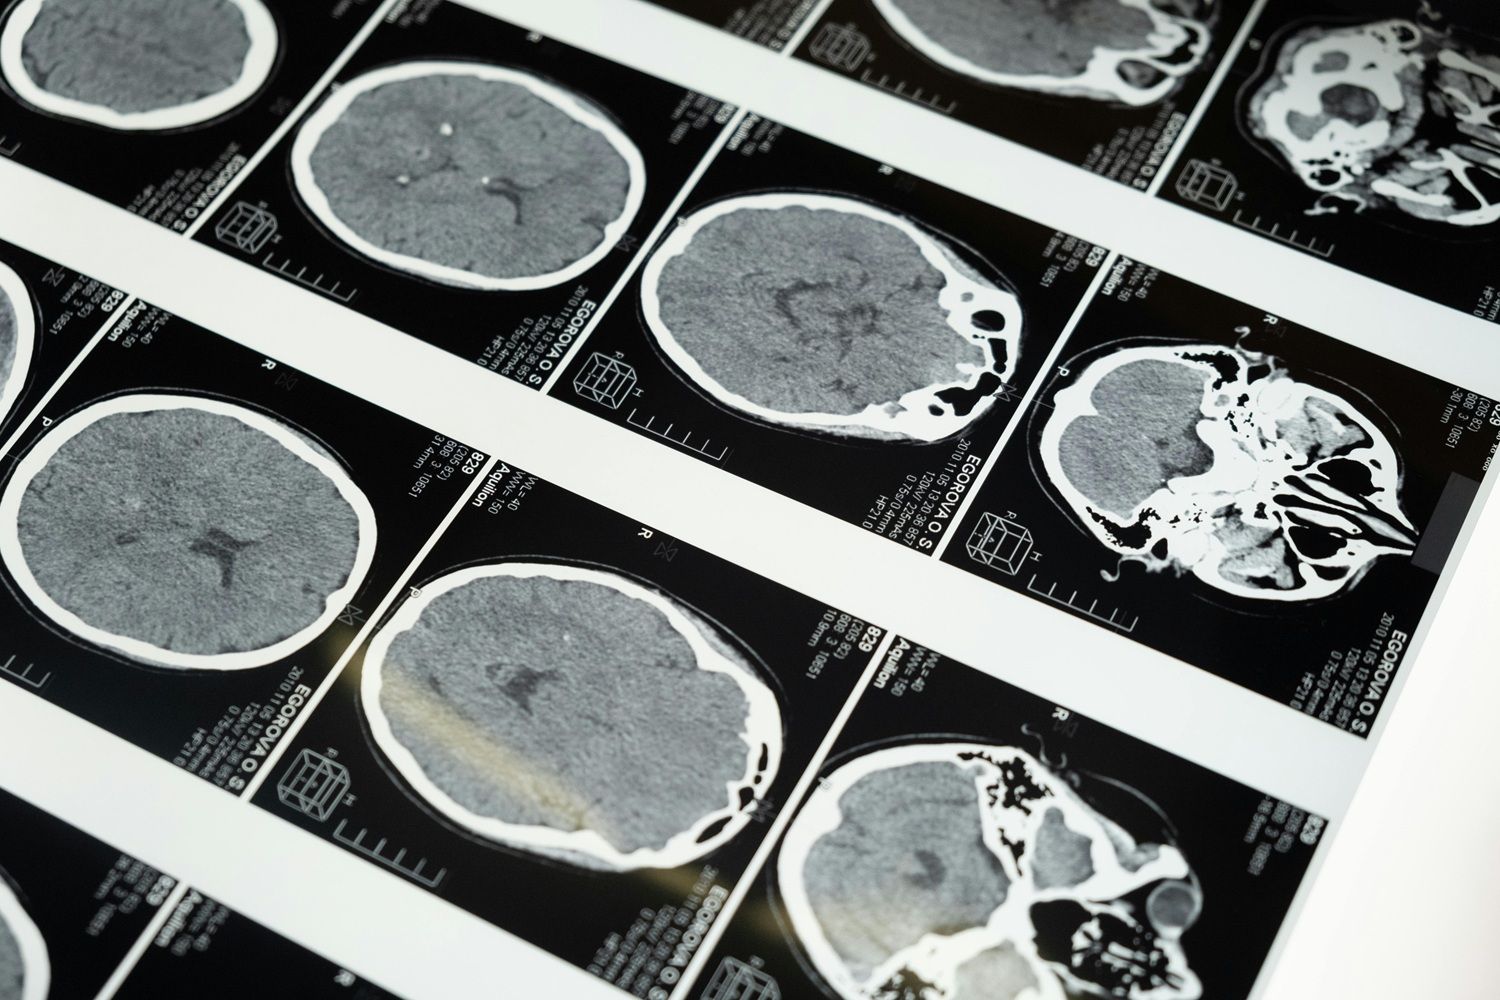

Na via contrária, uma pesquisa divulgada em julho de 2025 na revista Immunity, conduzida por neurocientistas da Universidade de Purdue, apontou que níveis elevados de LDL entre os 40 e 65 anos aumentam significativamente o risco de Alzheimer e outras demências nas décadas seguintes. O estudo identificou que o excesso de gordura sobrecarrega as microglias — células responsáveis pela defesa e limpeza do cérebro — e faz a enzima lipídica DGAT2 se acumular nessas estruturas, prejudicando a eliminação de placas amiloides.

Em culturas celulares, ao eliminar as enzimas de gordura, os cientistas viram a função dessas “faxineiras” se recuperar totalmente.